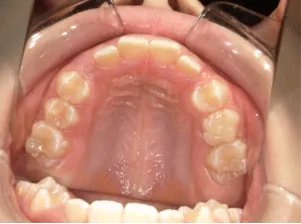

治療中③中1:非抜歯治療の診断で、上顎に歯の生えるスペースをつくるため上顎左右6をプレートで遠心移動し、隙間ができた時点

*マルチブラケット法移行前

*マルチブラケット法移行後

治療中④中1:治療中 マルチブラケット法へ移行

| 行ったご提案・診断内容 | 生え変わりが終わってなくマルチブラケット法による咬合治療には早い時期のため、顔立ちの成長を促す目的で歯列弓(アーチ)の拡大と前歯を並べながら永久歯が生えるのを待ち、咬合治療開始時に再診断で抜歯、非抜歯を最終検討する提案をしました。 再診断時(写真②)、歯列の拡大と上顎前歯の並べ替えはされていましたが八重歯となったため抜歯、非抜歯を検討しました。 口元は特に問題がなく非抜歯で八重歯を改善するためのスペースを作ることが可能なため非抜歯治療を提案しました。 治療は、 ・拡大および上顎左右6を遠心移動させてスペースを作る 予定装置 |